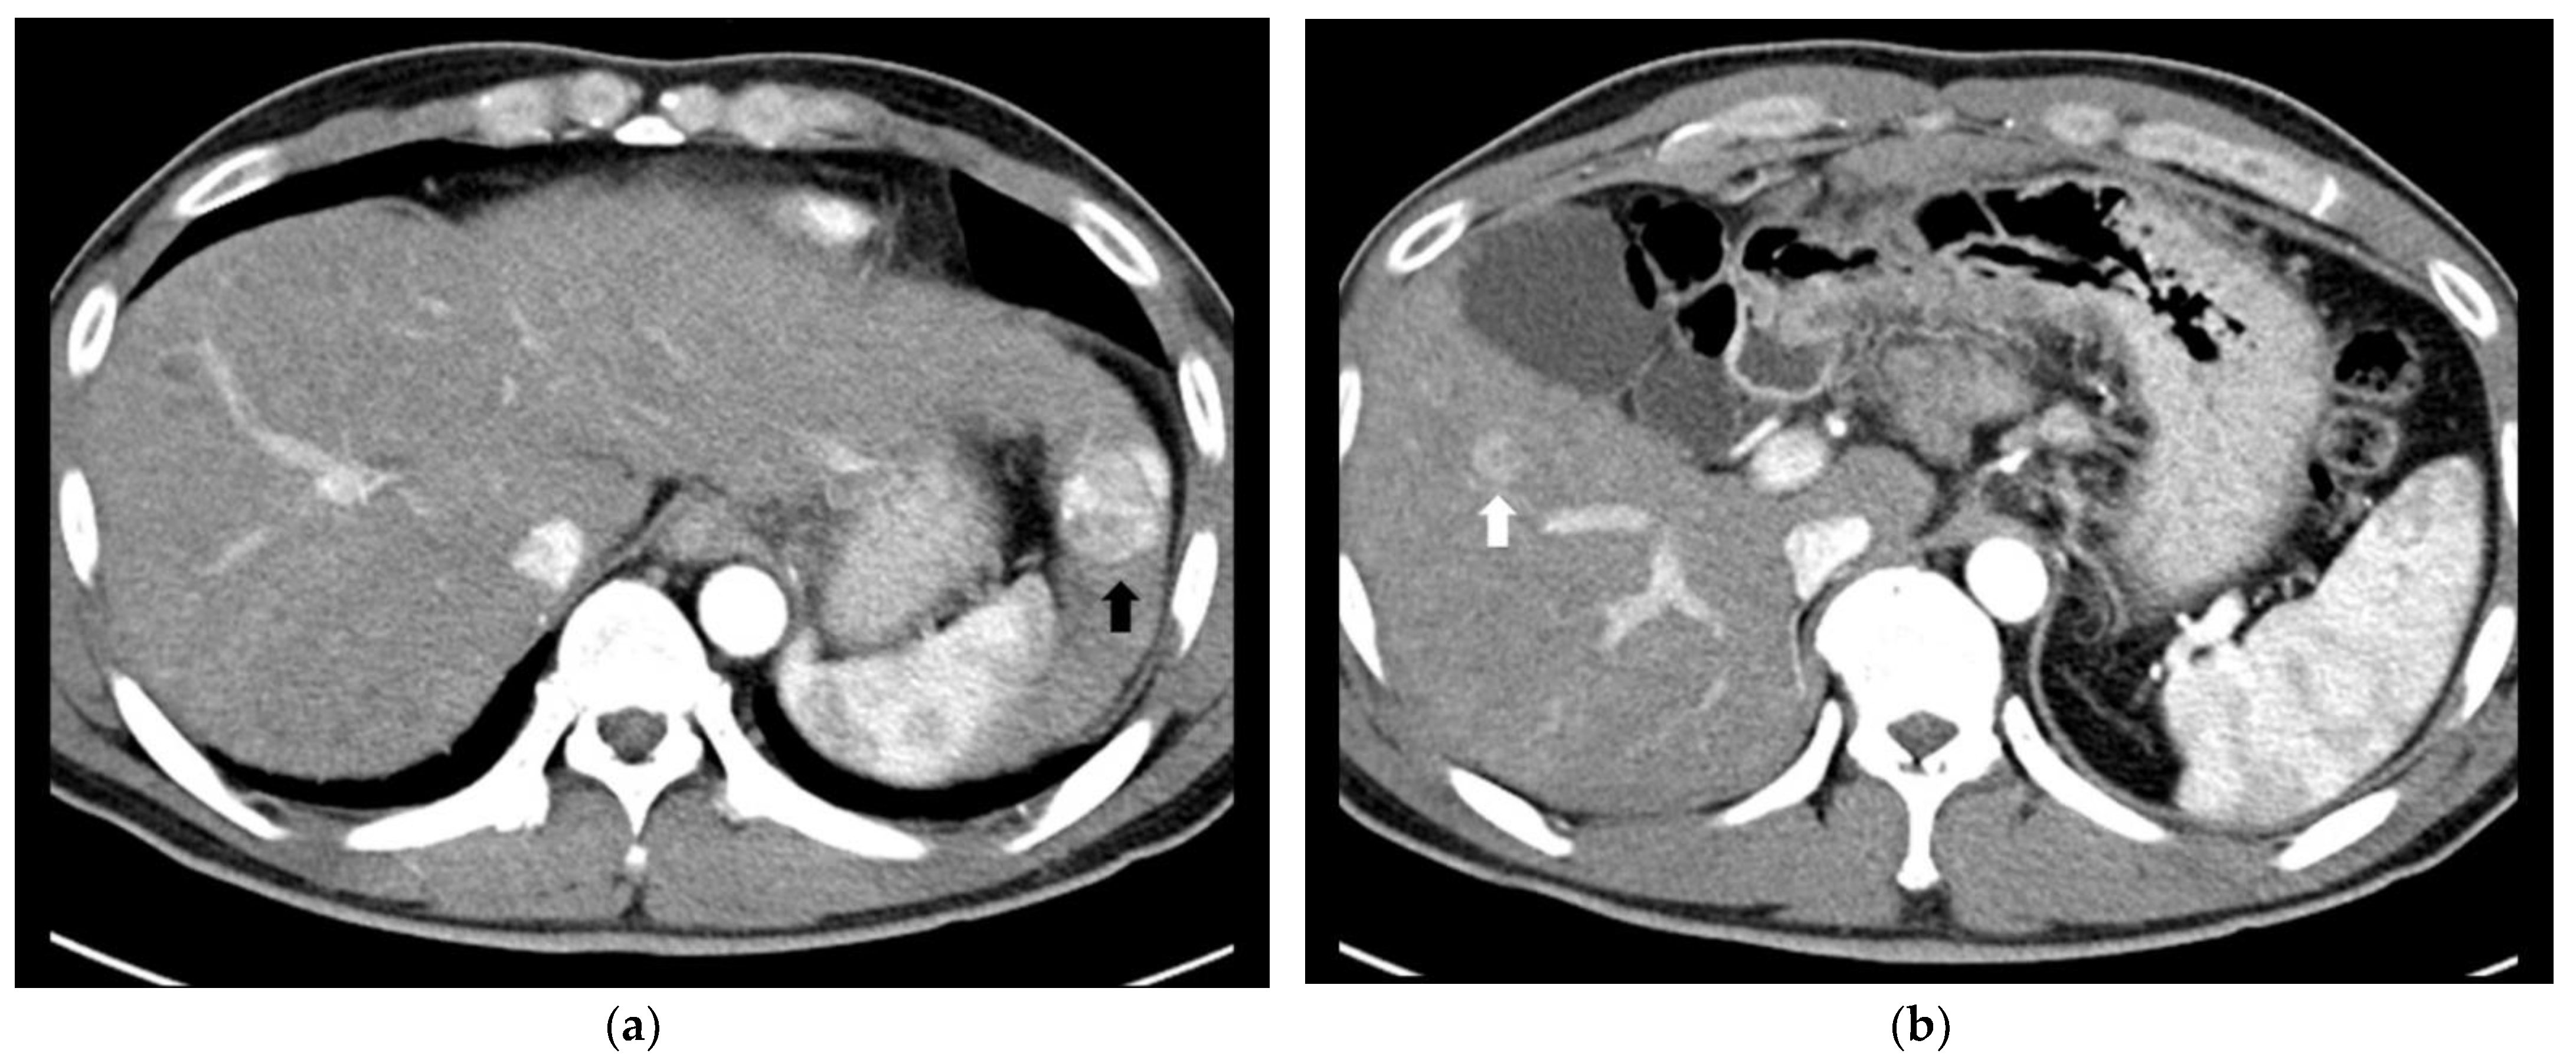

2.2. Surgical Resection plus Intraoperative Radiofrequency Ablation

- Park, H.S.; Kim, Y.J.; Yu, M.H.; Jung, S.I.; Jeon, H.J. Real-time contrast-enhanced sonographically guided biopsy or radiofrequency ablation of focal liver lesions using perflurobutane microbubbles (sonazoid): Value of Kupffer-phase imaging. J. Ultrasound Med. 2015, 34, 411–421. [Google Scholar] [CrossRef] [PubMed] [Green Version]